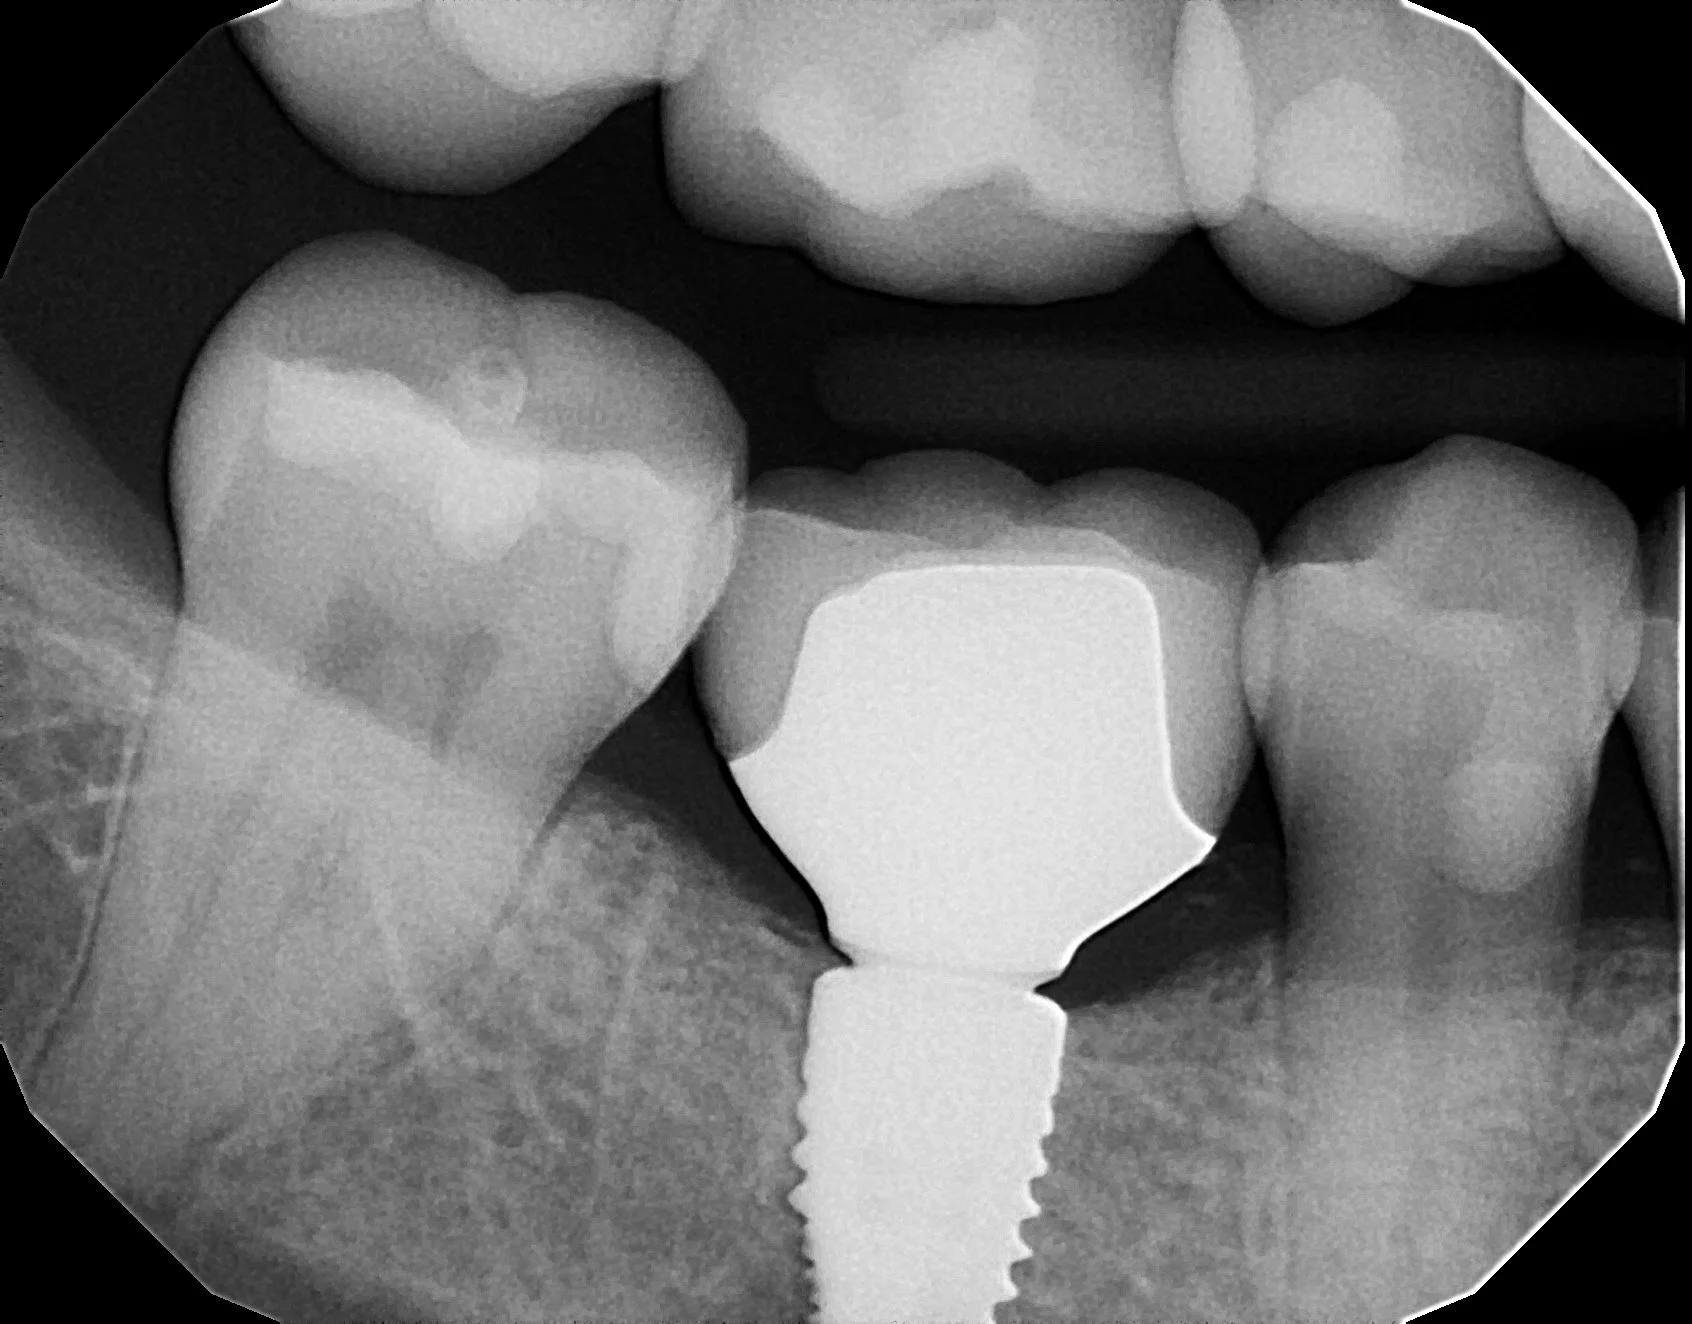

Implant Restorative Applications Welcome to Dr. Klim's Online CEREC training. Please choose from the following channel menu to view all the videos: Implant CEREC Software Workflows View Videos View Videos Implant Tibase and Scanning View Videos View Videos Implant Milling and Material Choice View Videos View Videos Implant Restoration Finishing View Videos View Videos Implant Seating- One and Two Piece View Videos View Videos Implant Restorative Case Review View Videos View Videos